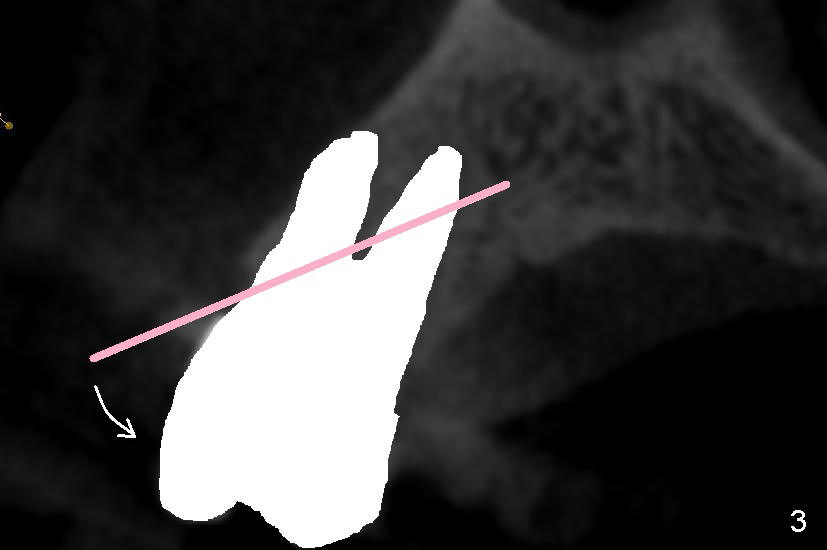

Even in a single root socket, osteotomy is to be created in the palatal wall. To get a "catch", a drill or osteotome (RT for example; Fig.3 pink line) is placed more or less perpendicular to the palatal wall. Once the catch is achieved, the axis of osteotomy is changed (Fig.3 curved arrow), more or less parallel to the bone morphology (buccal and/or palatal walls, Fig.4). Gradually the osteotomy is increased in diameter (Fig.5 pink area). In the single root, a separate, palatal socket has been created with formation of a septum. Subsequently, taps and the implant (tapered, Fig.6 red portion) will push the existing or just formed septum buccally (from yellow area to grey area). The fractured and displaced septum is going to participate in repairing the buccal apical defect if the pre-existing infection is under control under protocol proposed by Tatum group.